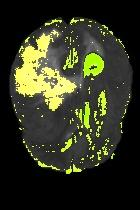

Current unsupervised anomaly localization approaches rely on generative models to learn the distribution of normal images, which is later used to identify potential anomalous regions derived from errors on the reconstructed images. However, a main limitation of nearly all prior literature is the need of employing anomalous images to set a class-specific threshold to locate the anomalies. This limits their usability in realistic scenarios, where only normal data is typically accessible. Despite this major drawback, only a handful of works have addressed this limitation, by integrating supervision on attention maps during training. In this work, we propose a novel formulation that does not require accessing images with abnormalities to define the threshold. Furthermore, and in contrast to very recent work, the proposed constraint is formulated in a more principled manner, leveraging well-known knowledge in constrained optimization. In particular, the equality constraint on the attention maps in prior work is replaced by an inequality constraint, which allows more flexibility. In addition, to address the limitations of penalty-based functions we employ an extension of the popular log-barrier methods to handle the constraint. Comprehensive experiments on the popular BRATS'19 dataset demonstrate that the proposed approach substantially outperforms relevant literature, establishing new state-of-the-art results for unsupervised lesion segmentation.

翻译:目前未受监督的异常本地化方法依靠基因模型来了解正常图像的分布,这些模型后来被用于确定从重建图像错误中得出的潜在异常区域。然而,几乎所有先前文献的主要局限性是,需要使用异常图像来设定一个特定等级的阈值以定位异常。这限制了其在现实情景中的可用性,在现实情景中,只有通常能获取正常数据。尽管存在这一重大缺陷,但只有少数作品通过在培训中整合对关注地图的监督,解决了这一局限性。在这项工作中,我们提议了一种新颖的提法,不要求使用异常图像来界定阈值。此外,与最近的工作相反,拟议的限制是以更加有原则的方式拟订的,在限制优化时利用众所周知的知识。特别是,先前工作中对关注地图的平等性制约被一种不平等性制约所取代,这允许更大的灵活性。此外,为了解决基于惩罚的功能的局限性,我们采用了流行的日志障碍方法来应对这一制约。我们建议对流行的BRATS'19数据设置进行综合实验,这与最近的工作不同,因此,拟议的限制是以更加有原则的方式提出了限制,即拟议的方法大大地超越了相关的分段结果。